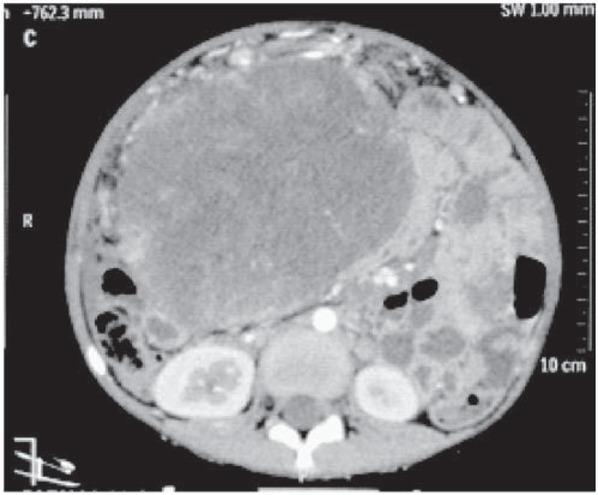

The girl was pale with massive abdominal distension and mild respiratory distress. A large 12 cm x 12 cm firm mass arising from the pelvis was palpable and occupied almost all of the abdomen. Blood investigations suggested anaemia. Lactate Dehydrogenase and Alpha-FetoProtein were raised (1143 U/l and more than 1000). Computed Tomography suggested a large solid cystic adnexal/ ovarian mass with septations and pedunculated serosal deposits on sigmoid colon and mild ascites suggesting neoplastic etiology (fig. 1 and 2).

Fig. 1

CT scan (axial section) showing the large solid cystic pelvic mass with septations.